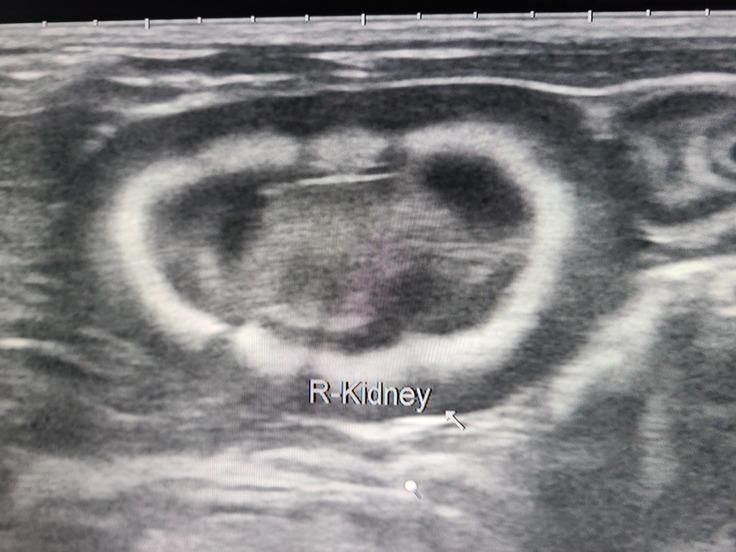

先天性または感染性の腎盂腎炎で、腎臓の形がどう見てもおかしい。左右ともボコボコ。

腎エコーの画像。

※撮影、掲載は許可を取っています。